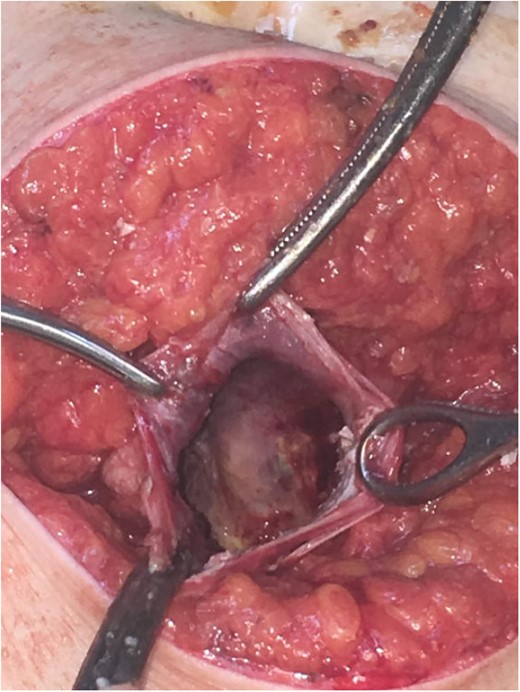

Subsequently, surgical exploration was performed. A preperitoneal sizable cyst was revealed, which developed in the abdominal wall without the involvement of any abdominal viscera or wall peritoneum. The macroscopic appearance of its content suggested that the mass was indeed a hydatid cyst (Figs 4 and 5). Incision upon the cyst wall and evacuation of its content were performed, without spilling of the content. Hypertonic solution of sodium chloride (NaCl 15%) was then injected in the remaining cavity, followed by the placement of a Pezzer catheter.

Intra-operative finding. Cyst content, indicating a hydatid cyst.